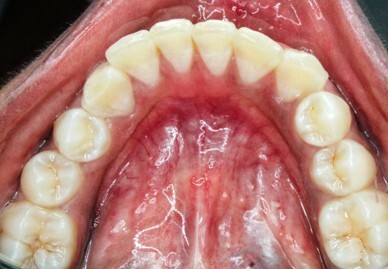

The MGJ was delineated by the visual method and the roll method following clinical examination in dental chairs appropriately equipped. Visual assessment relies on identifying the color difference between the gingiva and alveolar mucosa. The mucosa beyond the MGJ typically appears darker red compared to the AG, helping to demarcate the MGJ. The rolling probe method entails pushing the neighboring alveolar mucosa coronally with the blunt end of a probe. It is a functional assessment method that aids in determining the boundary between gingiva and movable mucosa.10 The probing sulcus depth was subtracted from the measured KG width at the mid-lingual aspect of each tooth to determine the width of AG, and all fractional measurements were rounded off to the nearest whole number of millimeters (Figure 1 through Figure 3).

Fig 1 through Fig 3. Measurements of lingual attached gingiva: Fig 1 = identifying the MGJ.

Figure 1

Fig 2 = sulcus depth measurement.

Figure 2

Fig 3 = determining width of keratinized gingiva.

Figure 3